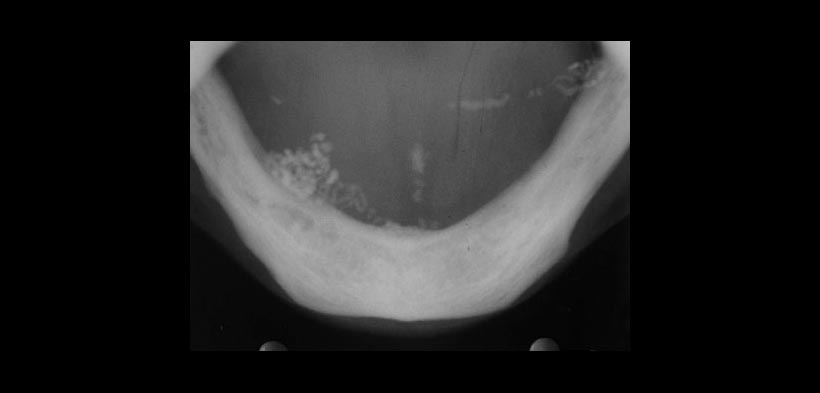

Fig. 2. Radiografía oclusal inferior de la misma paciente, que muestran las calcificaciones

en el piso de boca.